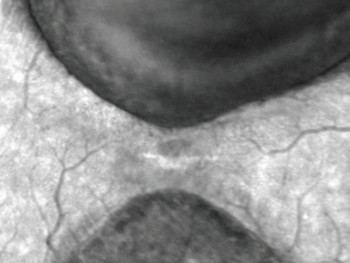

Nesta nova tecnologia pode se realizar auto-fluorescência que é uma frequencia que capta os brilhos prórprios dos tecidos. Pode ser útil em avaliar drusas e auxiliar no diagnóstico diferencial de lesões pigmentadas como nevus.